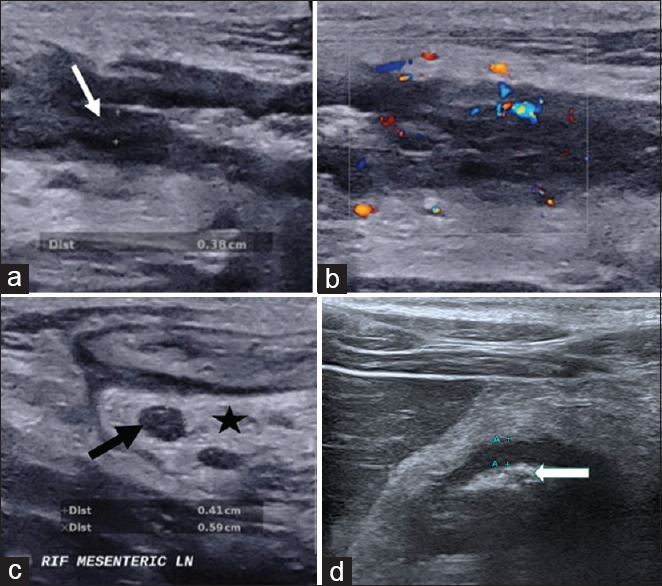

Methods: This is a prospective cross-sectional study of IUS performed on IBD patients in a tertiary centre. IUS parameters including intestinal wall thickness, loss of wall stratification, mesenteric fibrofatty proliferation, and increased vascularity were compared with endoscopic and clinical activity indices.

Results: Among the 51 patients, 58.8% were male, with a mean age of 41 years. Fifty-seven percent had underlying ulcerative colitis with mean disease duration of 8.4 years. Against ileocolonoscopy, IUS had a sensitivity of 67% (95% confidence interval (CI): 41-86) for detecting endoscopically active disease. It had high specificity of 97% (95% CI: 82-99) with positive and negative predictive values of 92% and 84%, respectively. Against clinical activity index, IUS had a sensitivity of 70% (95% CI: 35-92) and specificity of 85% (95% CI: 70-94) for detecting moderate to severe disease. Among individual IUS parameters, presence of bowel wall thickening (>3 mm) had the highest sensitivity (72%) for detecting endoscopically active disease. For per-bowel segment analysis, IUS (bowel wall thickening) was able to achieve 100% sensitivity and 95% specificity when examining the transverse colon.